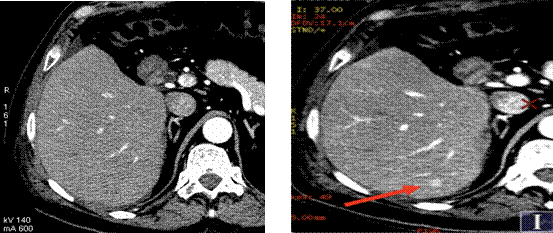

人体内的很多小病灶也同样容易被混合能量成像的常规CT所掩盖,但是在单能量成像下,这些小病灶会突显出来,这样,可以提高癌症早期诊断的能力。

传统CT成像,未显示病灶 40keV单能量下诊断病灶